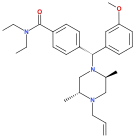

Diphenylmethylpiperazines